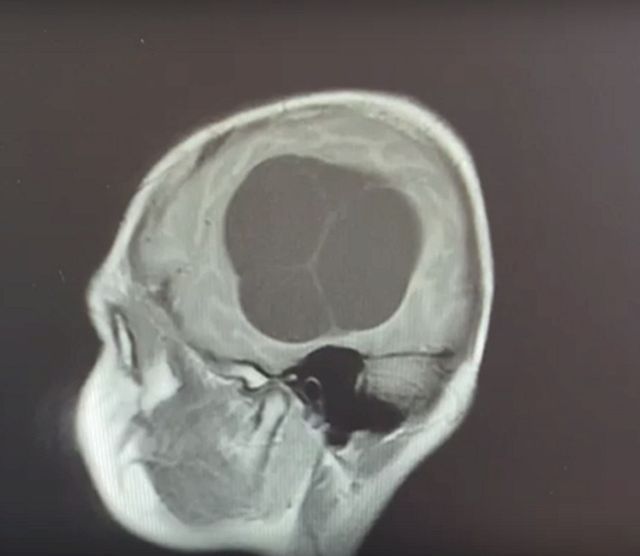

Киста В Голове Фото

Киста В Голове Фото 146 фотографий